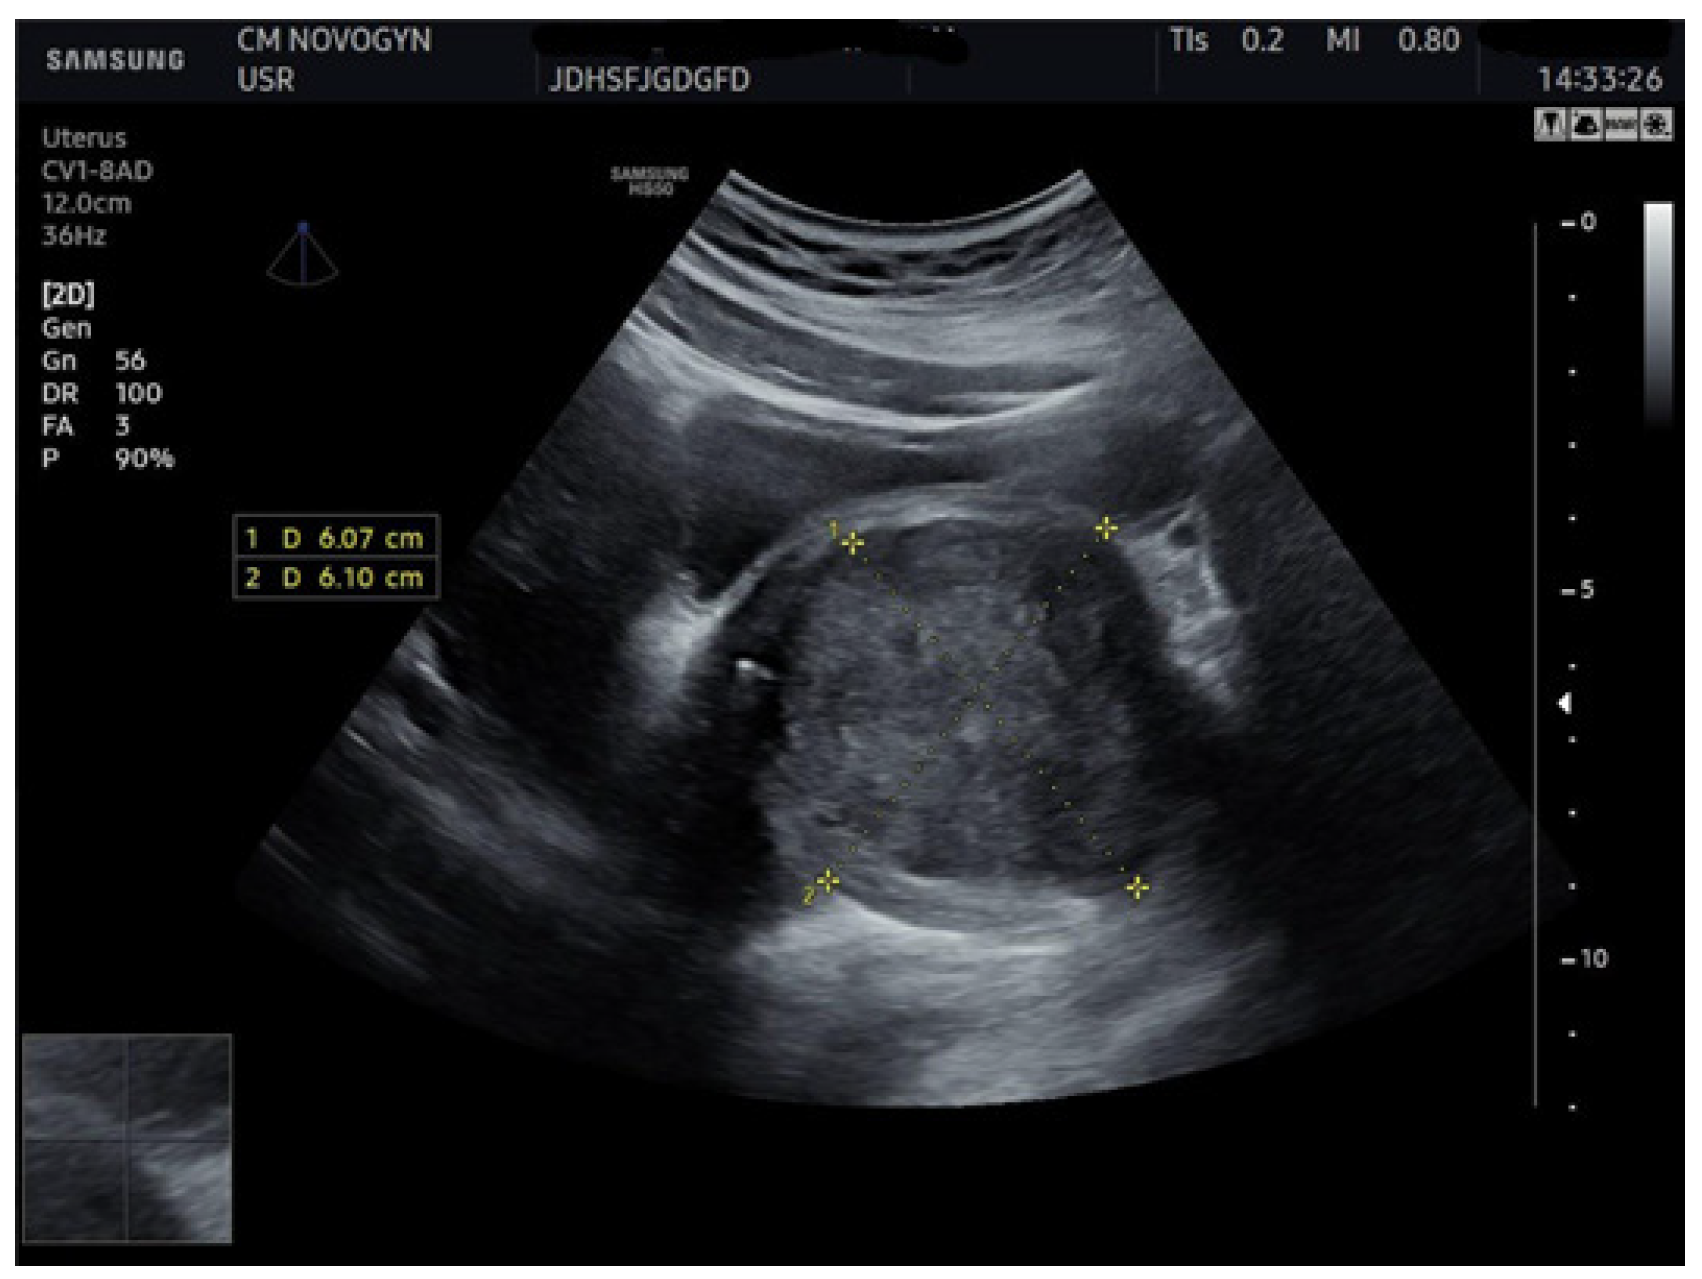

Additional abdominal ultrasonography confirmed a well-circumscribed mass measuring 6.07 × 6.10 cm from alternative imaging planes, demonstrating consistency with initial findings (Figure 2).

Abdominal ultrasonographic image visualizing the well-demarcated, solid, hypoechoic mass (calipers) in the vesicovaginal region measuring (6.07 × 6.10) cm, confirming a consistent solid nature.